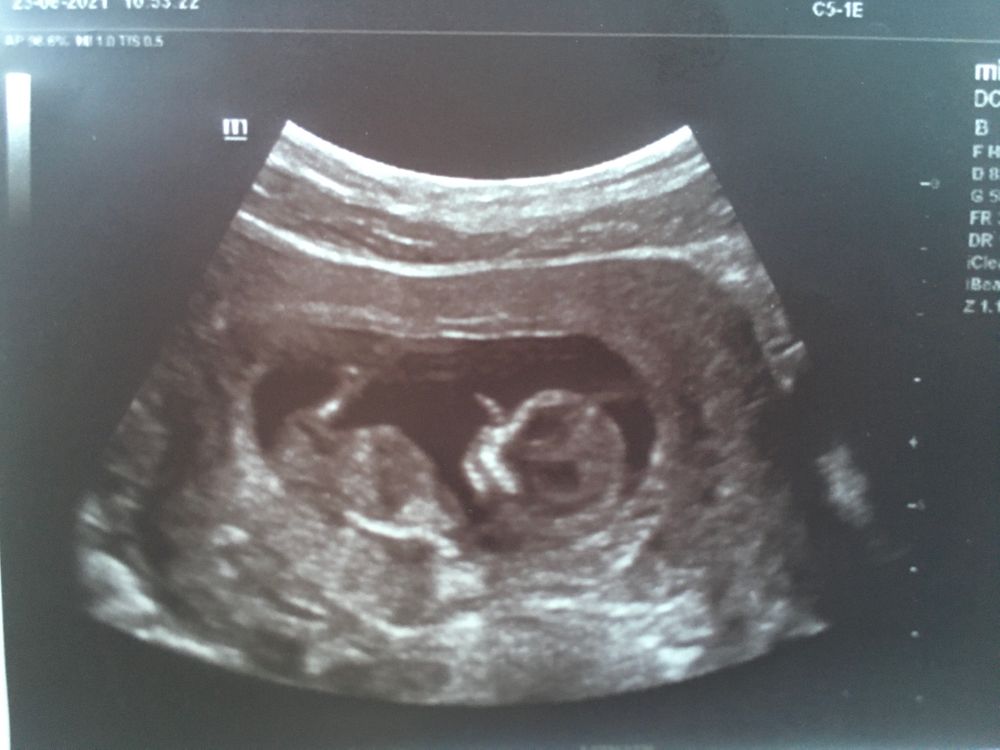

Бугорок не видно 🤷‍♀️ Изображение У нас чётко получилось на видео , сомнений не было

У меня в точь такое же фото. Думаю мальчик

Не понятно…

Не видно половой бугорок...

Не видно у вас, бугорок прикрыл ножкой. можно только погадать)

Мальчик скорее всего, бугорок спрятан за ножкой